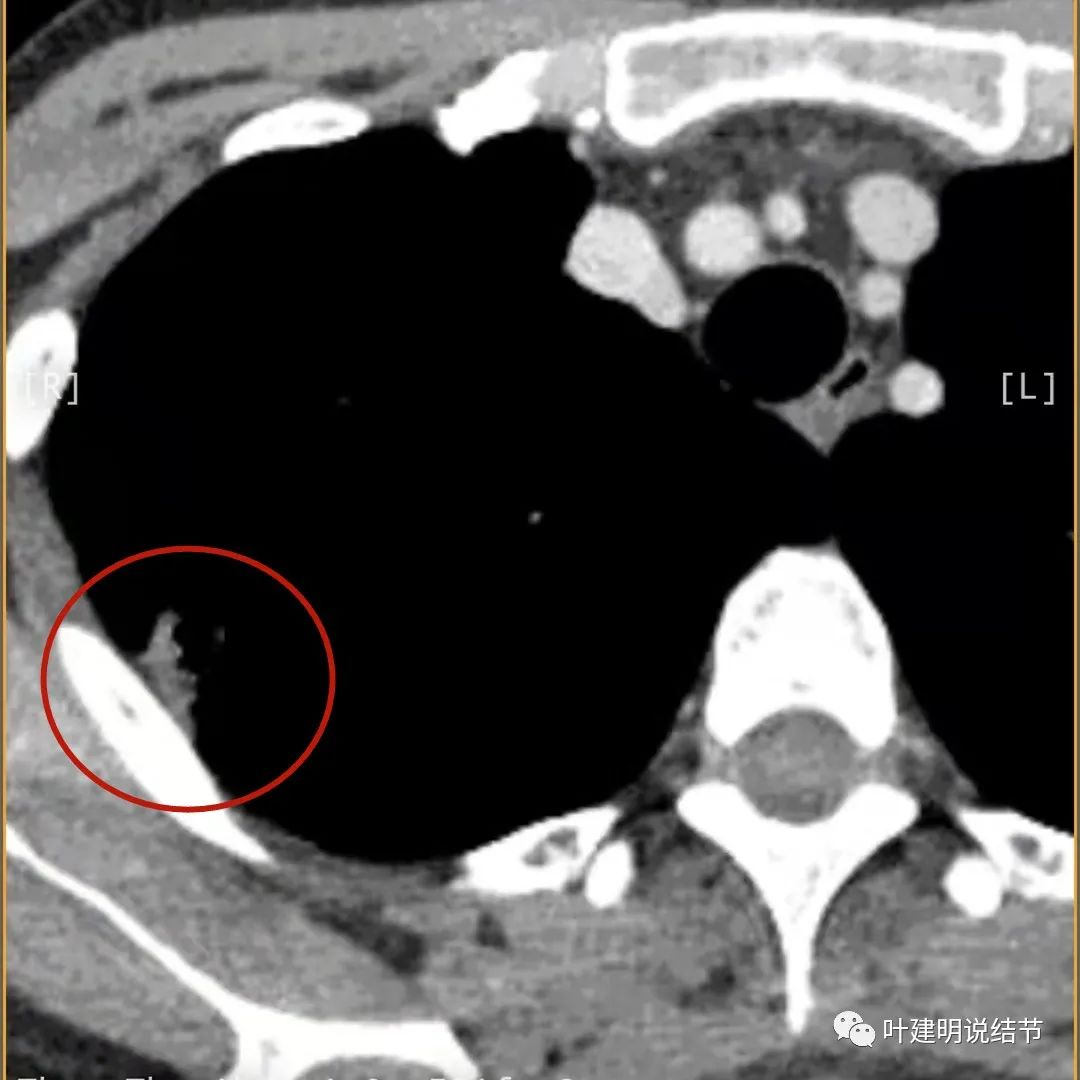

蓝色箭头所指处居然有低密度影,难道是坏死?因为比肌肉密度低,也无强化,况且主病灶的中间也有个低密度的小点状

病灶有明显强化(说明炎性可能性大,如果恶性这样强化,血供丰富,应该倍增速度更快。蓝色箭头示胸膜处低于软组织密度的区域;桔色箭头示病灶边缘平直缺乏膨胀性;黄色箭头示中间的空腔

邻近胸膜处的增厚密度低于肌肉组织,病灶强化明显且均匀

此层也见明显的低密度区域(天蓝色箭头)

胸膜处明显增厚伴低密度区域

天蓝色箭头示病灶低密度区,考虑坏死可能性大,桔色箭头示边缘凹陷无膨胀性

上图示空洞偏心,而且红色箭头所指处与空腔似乎是整合,而非囊壁生长增厚。天蓝色箭头示近胸膜处的低密度区域,考虑坏死成分,囊壁的邻近部分也是极低密度区域,也可能是干酪样坏死区